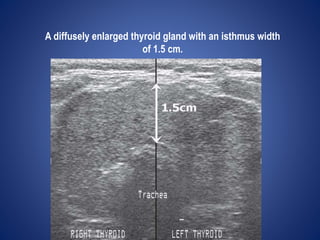

USG NECK

Thyroid is homogeneous & slightly hyperechoic.

The normal thyroid gland is 2 cm or less in both the transverse

dimension and depth, and is 4.5–5.5 cm in length& 0.5 mm ithmus.

A diffusely enlarged thyroid gland with an isthmus width

of 1.5 cm.